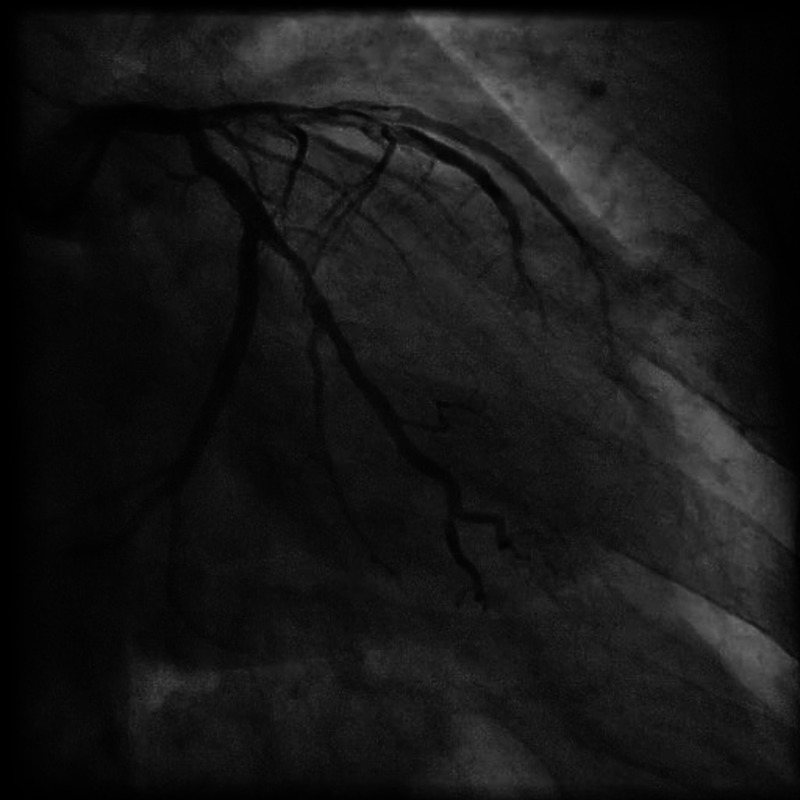

Figure 2.

Coronary angiogram LAO 02 CRAN 29 view, showing dissection in left anterior descending artery and first diagonal branch.